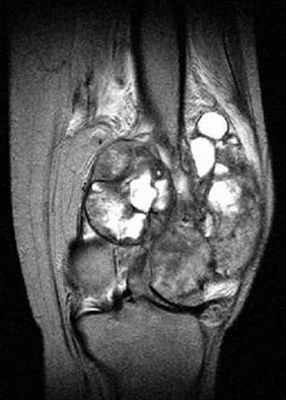

МРТ: чётко видимая хрящевая шапочка, имеющая геперинтенсивный сигнал на T2 (DP)-ВИ и изоинтенсивный сигнал на Т1-ВИ, неправильной формы и очень плотная (23 мм), принимающая дольчатый вид, вызывающая подозрение на саркоматозную дегенерацию. Периферическое повышение сигнала после инъекции.

>>>Типичный экзостоз (остеохондрома) = костная опухоль, поверхность которой покрытая хрящом. На ножке. Обычно встречается в метафизах, коленном суставе и проксимальном крае плечевой кости. Сканирование позволяет подозревать поражение мягких тканей хрящевым обызвествлением, но только МРТ позволяет определить толщину хрящевой шапочки, различаемой по гиперинтенсивному сигналу на Т2-ВИ и специфичному гипоинтенсивному сигналу на Т1-ВИ в активной фазе (гидратация++).

Толщина нормальной шапочки не должна превышать 10 мм у взрослого.

От 10 до 20 мм, поражение называется промежуточным.

Образование считается опухолевым, если оно превышает 20 мм.

IRM Pelvis Coronal Pondération DP